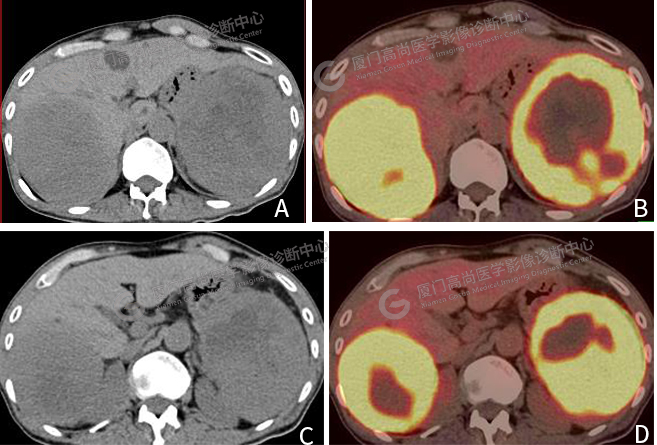

圖片圖3:A、 C CT圖像,肝臟右葉巨大腫塊影,脾臟內(nèi)巨大軟組織腫塊,代謝顯著增高。B、 D PET/CT融合圖像,腫塊代謝異常增高。

肝臟右葉見一巨大腫塊影,大小約10.0×8.6cm,F(xiàn)DG攝取明顯增高,SUVmax 16.1。脾臟內(nèi)見一巨大軟組織腫塊,大小約11.6×10.2cm,F(xiàn)DG攝取明顯增高,SUVmax 18.3(圖3)。